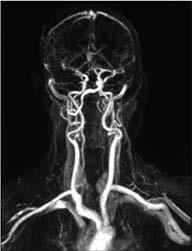

Darstellung hirnversorgender Gefäße

Extrakraniell: Das Verfahren der ersten Wahl ist sicher die FKDS (Abb. 1a–c). Als weitere Verfahren kommen dann die MRA (Abb. 2a, b) und gelegentlich auch die CTA zum Einsatz.

Abb. 2a

Abb. 2b

Abbildung 2a, b: Kontrastverstärkte MR-Angiographie (CE-MRA) der hirnversorgenden Gefäße.

a: Nachweis einer signifikanten ACI-Stenose rechts.

b: Ausschluss einer Dissektion der A. vertebralis bei C2-Fraktur.